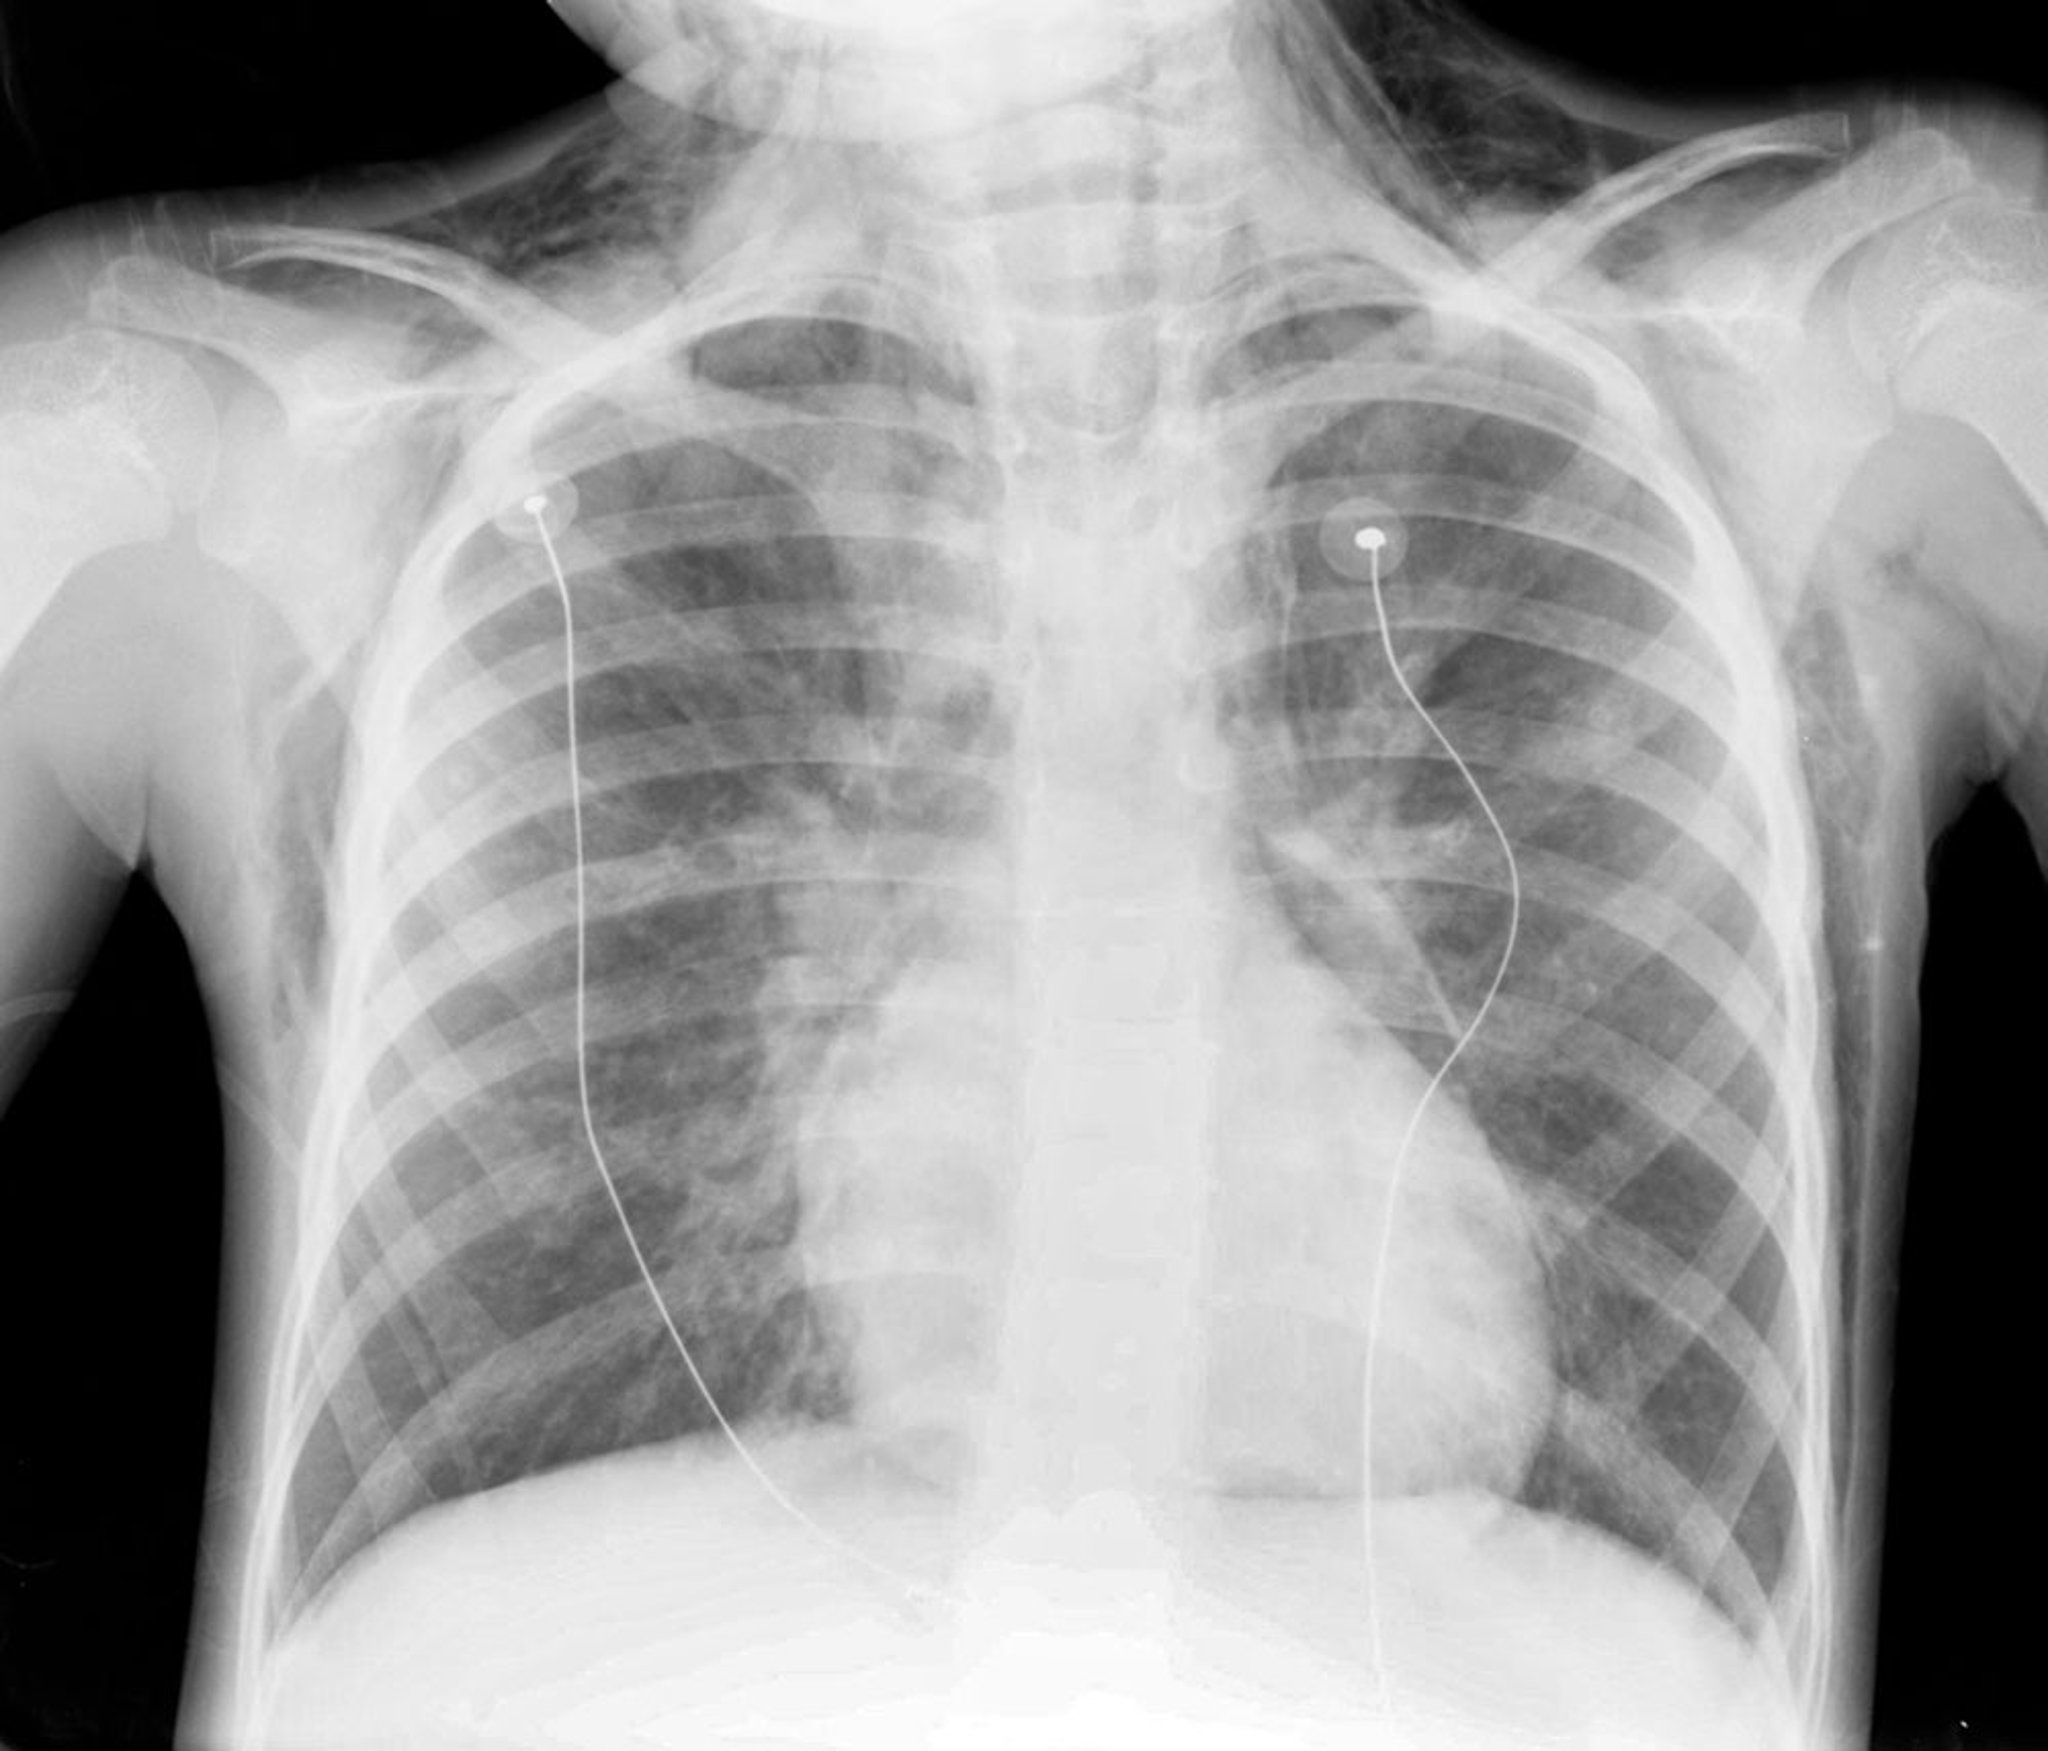

Le diagnostic est confirmé par la radiographie de thorax, qui montre de l'air dans le médiastin.